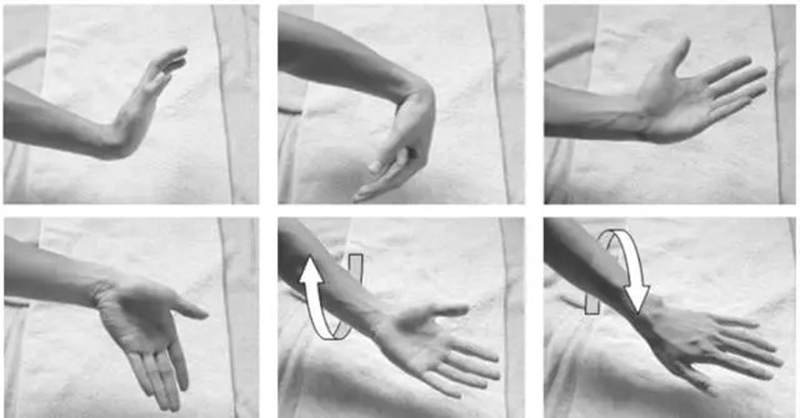

屈曲(Flexion):0°~90°

伸展(Extension):0°~70°

桡侧偏移(Radial Deviation):0°~15°

尺侧偏移(Ulnar Deviation):0°~45°

Sharpey's Test:患者坐姿椅子上,手臂放在桌子上,保持中立位,拳眼朝上。检查者一只手稳定远端桡尺关节,一只手握住手腕并给一个向内的压力,然后进行旋前旋后的动作。如果出现疼痛或咔嚓声则为阳性。

UTD Glide Test:患者坐位,手臂旋内放在桌子上,检查者先将拇指按在患者尺骨远端,再将食指按在患者豌豆骨上,然后慢慢用力挤压。两只手都要测试。如果产生疼痛或出现过度松弛,则为阳性。

Piano key test: 患者坐位,检查者一只手握着患者的手掌使前臂抬离桌面,并用另一只手的食指按压远端尺骨背侧(和掌侧),两只手都要测试。如果两只手尺骨松弛程度明显,则松弛侧的手为阳性。

TFCC Load Test:患者坐位,检查者一只手握住患者的前臂,另一只手握住患者手部,然后沿着中轴施加力量并将手腕向尺侧偏移,同时将手腕往背侧和掌侧移动或旋转前臂。如果此测试会引起TFCC处疼痛感、有喀、啪声则测试为阳性。